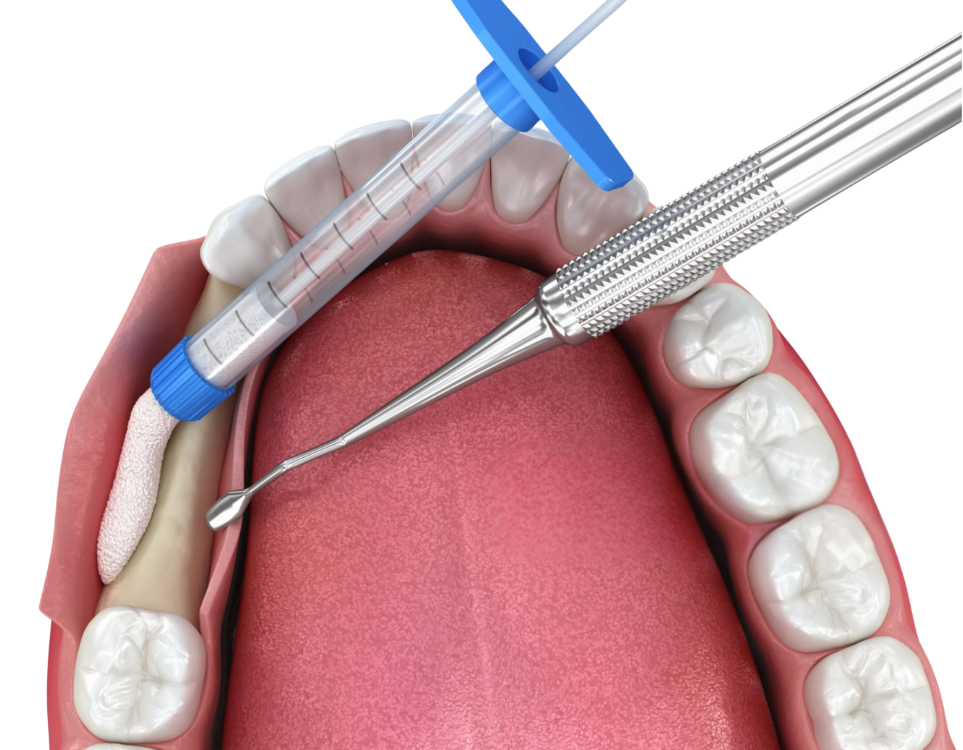

Chirurgie pré-implantaire

La préparation de la chirurgie pré-implantaire c’est l’ensemble des interventions chirurgicales dédiées à préparer le site implantaire. Elles peuvent intervenir au niveau osseux, au niveau gingival ou encore les deux.

Greffe de la Gencive / Chirurgie Mucco-Gingivale

Renforce la gencive autour des implants afin d’avoir un environnement implantair sain favorisant la pérennité de l’implant dans le temps. Trois cas de figure : Avant la pose d’implant, Durant la pose d’implant, après la pose d’implants.